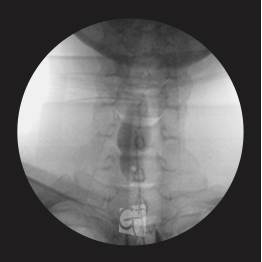

요추 신경성형술

-

꼬리뼈 구멍으로 카테타 삽입

-

척추관 안쪽으로 진입 약물 주입

-

원인부위 염증 제거 및 유착 박리

-

유착박리로 추간공 확보, 신경 압박 감소

-

척추관에서 약물이 잘 퍼져나오는 모습

-

허리 신경 전체를 효과적으로 치료